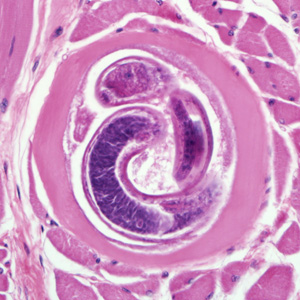

in wide range of hosts, human tissue

Eosinophila, muscle pain, ocular pain, pneumonia, petechial hemorrhage in conjunctiva and under nail beds

worldwide

history of eating undercooked/raw meat

Trichinella spiralis

encysted larva

Trichinellosis

ingestion of encysted larva in undercooked/raw meat